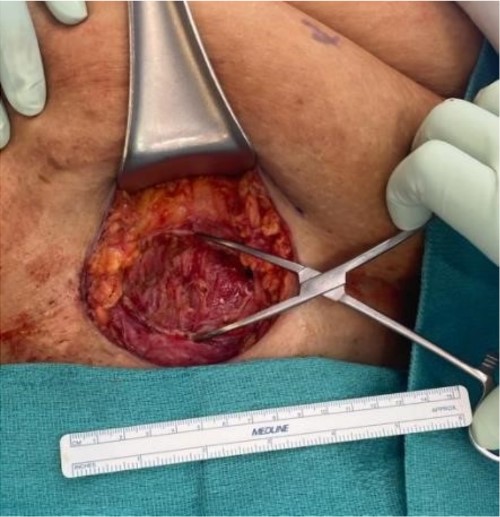

The mass was located in the subcutaneous tissue of the abdominal wall just deep to the previous Pfannenstiel scar and measured 7 × 6 × 4 cm. The mass invaded the anterior rectus fascia without extension into the rectus muscle and was excised en bloc with fascia and grossly negative margins (Fig. 4). Additional margins were excised circumferentially to ensure no further remnant of endometrial cells. The defect measured approximately 12 cm and was closed with synthetic mesh (Fig. 5). Histopathology revealed endometrioma with all margins negative for endometriosis (Figs 6–8). At her postoperative visit, the patient reported complete resolution of symptoms even throughout her most recent menstrual cycle after excision.